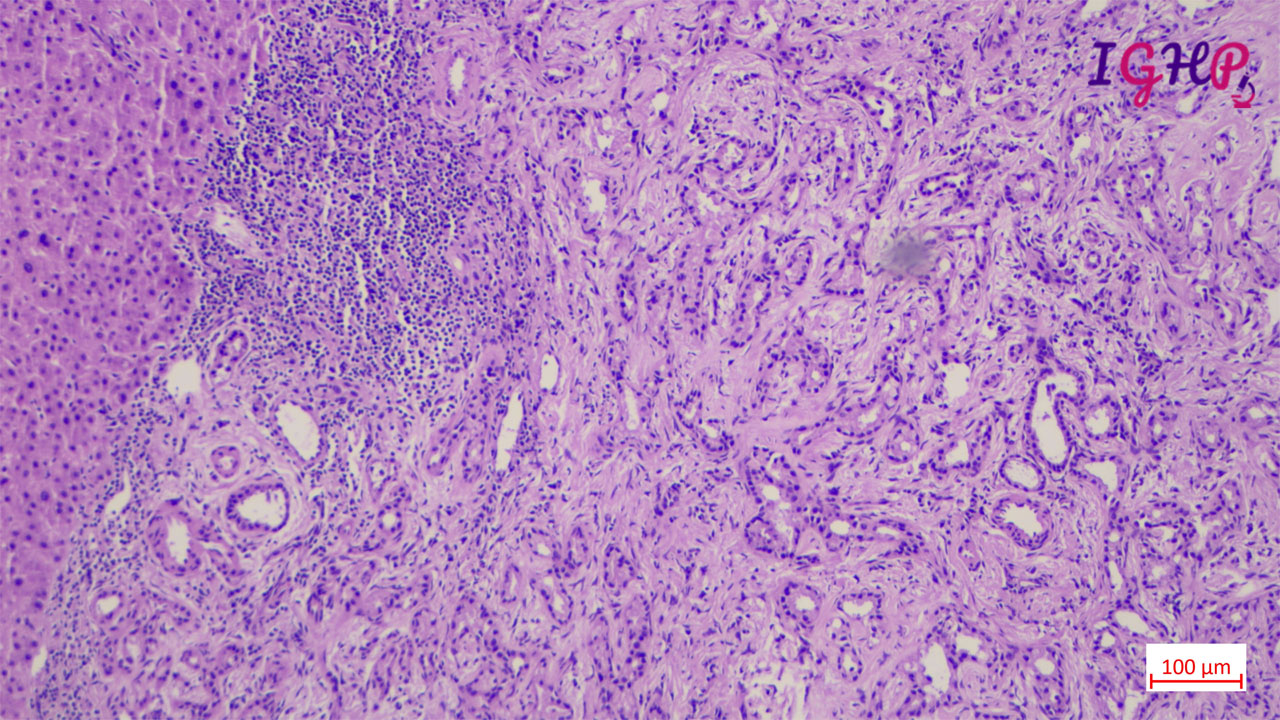

Microscopic examination showed an unencapsulated proliferation of uniformly spaced ductules lined by bland, cuboidal epithelium in a collagenous stroma. The architecture seems non-infiltrative, with evidence of entrapped native portal tracts present within the lesion itself.

BDA is an important diagnosis in frozen section examination. This needs to be differentiated from malignant nodules. Peripheral subcapsular location, presence of portal tracts within the lesion, inflammatory infiltrate and mild atypia favours a bile duct adenoma. Immunohistochemistrywith lowKi67 and wild type p53 may be used as adjunct.